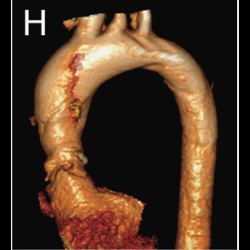

Primary aortic thrombus in young a rare site

Primary aortic thrombus in young: a rare site, a novel treatment

Primary aortic thrombus in young a rare site

Primary aortic thrombus in young: a rare site, a novel treatment